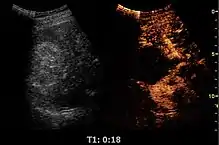

Solid malignant tumors in the kidney do not exhibit specific enhancement patterns like some liver lesions, and no valid enhancement criteria between benign and malignant renal lesions have been proposed. However, CEUS is used in some patients after ablation of renal cell carcinoma to evaluate contrast uptake in the treated area (Figure 30).

Figure 31. Unspecific cortical lesion on CT is confirmed cystic and benign with contrast-enhanced ultrasound (CEUS) using image fusion.[1]